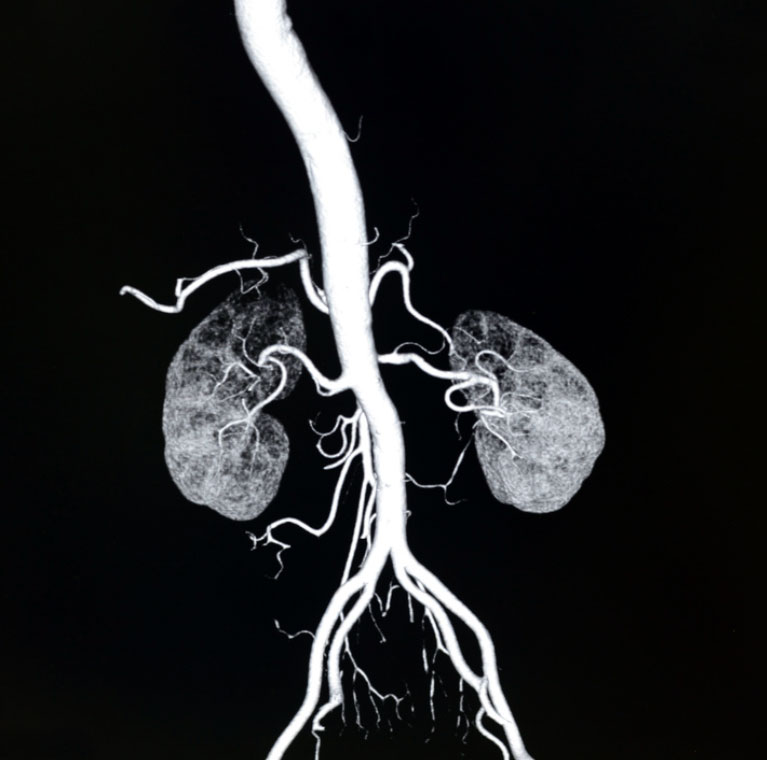

Image

Renal Arteries

(CT Scan)